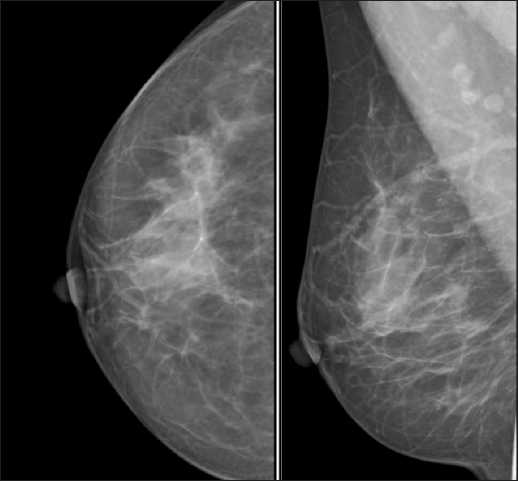

Обзорная маммография молочных желез в 2 проекциях через 4 мес после первичного обследования: в правой молочной железе визуализируются единичные мелкие тени кистозного характера, рассеянные кальцинаты. Отдельные узловые образования, зоны асимметрии строения и перестрой-

Рис. 3. Маммограммы в прямой и косой проекциях. Примечание: рисунок выполнен авторами

Fig. 3. Mammograms in straight and oblique projections. Note: created by the authors

ки структуры не определяются. Аксиллярные лимфатические узлы визуализируются с жировыми воротами, в видимой части аксиллярная область без особенностей. Rg-картина остаточных фиброзно-кистозных изменений обеих молочных желез. BI-RADS-2 слева и справа (рис. 3).